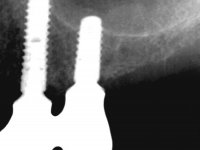

A reabilitação proposta, consistia na colocação de uma ponte metalo-cerâmica implanto-suportada no 2º quadrante, evitando-se a prótese esquelética. Após a realização do estudo imagiológico, seria decidido definitivamente, o número e localização dos implantes a colocar. A paciente não mostrou interesse na substituição da ponte metalo-cerâmica antero-superior.

O estudo imagiológico para a colocação dos implantes, começou com a realização em laboratório de uma guia com dentes em sulfato de bário. Esta guia foi colocada em boca conjuntamente com marcas de referência coladas aos dentes, também em sulfato de bário. A guia foi estabilizada com cera mole. A TAC foi realizada com estas referências colocadas em boca. Após a realização da TAC foi feita uma impressão de arrasto em silicone. Esta impressão foi vazada a gesso em laboratório e posteriormente digitalizada. A digitalização do modelo com as referências foi sobreposta á imagem da TAC, permitindo uma planificação apurada na colocação dos implantes. Na planificação foi decidido colocar 2 implantes no local dos dentes 2.3 e 2.4 evitando-se a zona do 2.2 com pouco osso e o seio maxilar. Este estudo deu origem a uma guia cirúrgica que orientou a colocação dos implantes. Durante o período de osteo-integração a paciente utilizou a prótese removível rebasada com acondicionador de tecidos. A guia cirúrgica mostrou-se também útil na exposição dos implantes mostrando a sua localização precisa e orientando a incisão. A impressão definitiva foi realizada utilizando a técnica de moldeira aberta após eliminação do attachment. No laboratório foi confeccionada uma ponte metalo-cerâmica de 3 elementos com o elemento 2.2 em suspensão. A ponte após verificação e aprovação foi cimentada. A reabilitação apesar de pouco extensa (sem o elemento 2.6) mostrou-se capaz estetica e funcionalmente.